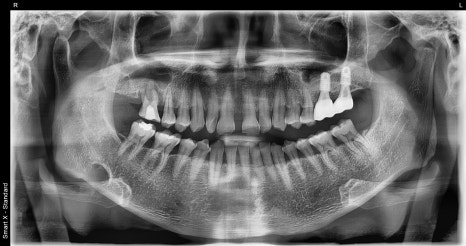

Left photo: panoramic X-ray taken at the patient’s first visit.

Right photo: initial intraoral photo showing the condition of the gums and teeth in the molar area.

The large molar at the very back had already been missing at the first visit, and the molar in front of it had severe periapical inflammation.

In addition, the small molar was severely mobile, so both teeth were extracted and replaced with implants, while overall gum treatment was also performed to establish the treatment plan.